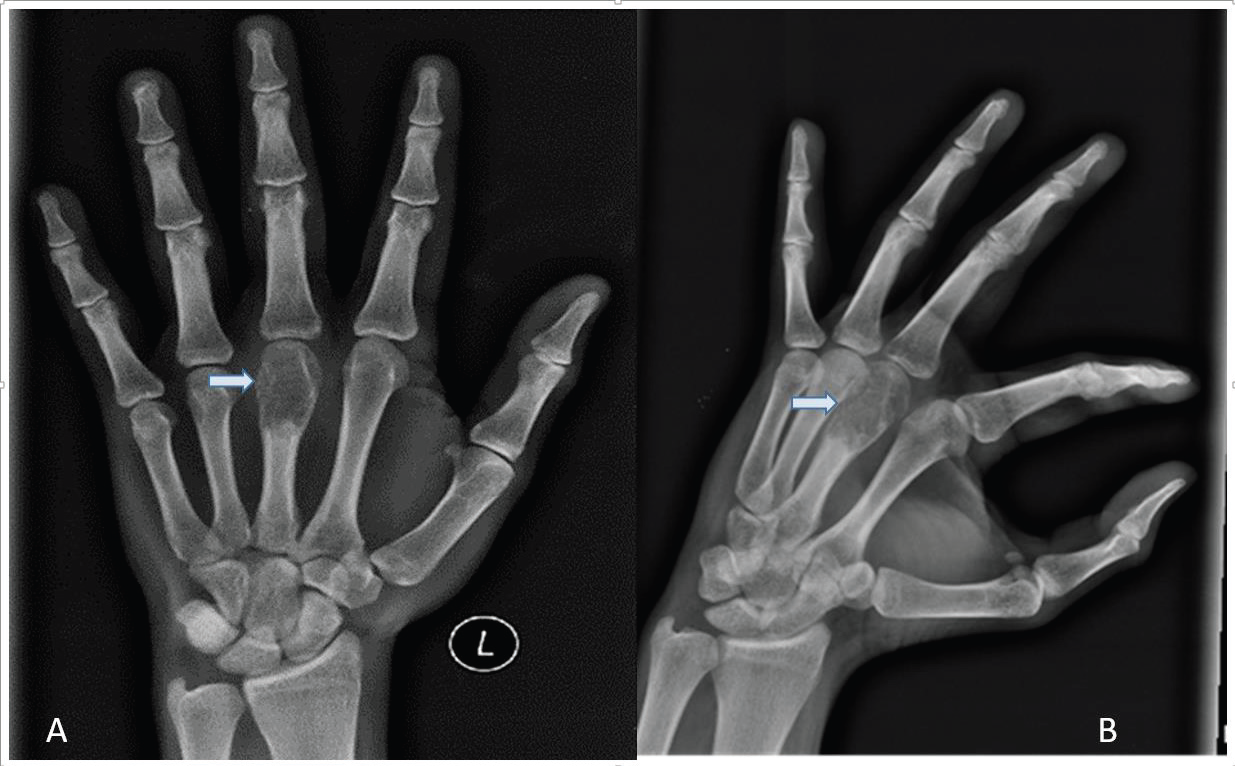

AP Radiograph of left hand revealed a mild expansile lytic lesion with thin septations and a narrow zone of transition, involving the head and proximal shaft of the third metacarpal bone, without periosteal reaction or soft tissue involvement [Figure 2]. The differential diagnosis considered were enchondroma, aneurysmal bone cyst, and tuberculous dactylitis.

Figure 2:Radiograph of left-hand AP (A) and oblique view (B) showing mild

expansile lytic lesion with thin septations and a narrow zone of transition,

involving the head and proximal shaft of the third metacarpal bone, without

periosteal reaction and with minimal soft tissue involvement.